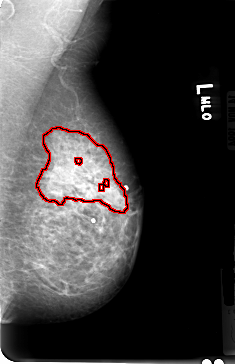

B_3030_1.LEFT_MLO

FILE: B_3030_1.LEFT_MLO.OVERLAY

TOTAL_ABNORMALITIES 1

ABNORMALITY 1

LESION_TYPE CALCIFICATION TYPE PUNCTATE DISTRIBUTION SEGMENTAL

ASSESSMENT 4

SUBTLETY 2

PATHOLOGY MALIGNANT

TOTAL_OUTLINES 4

BOUNDARY

CORE